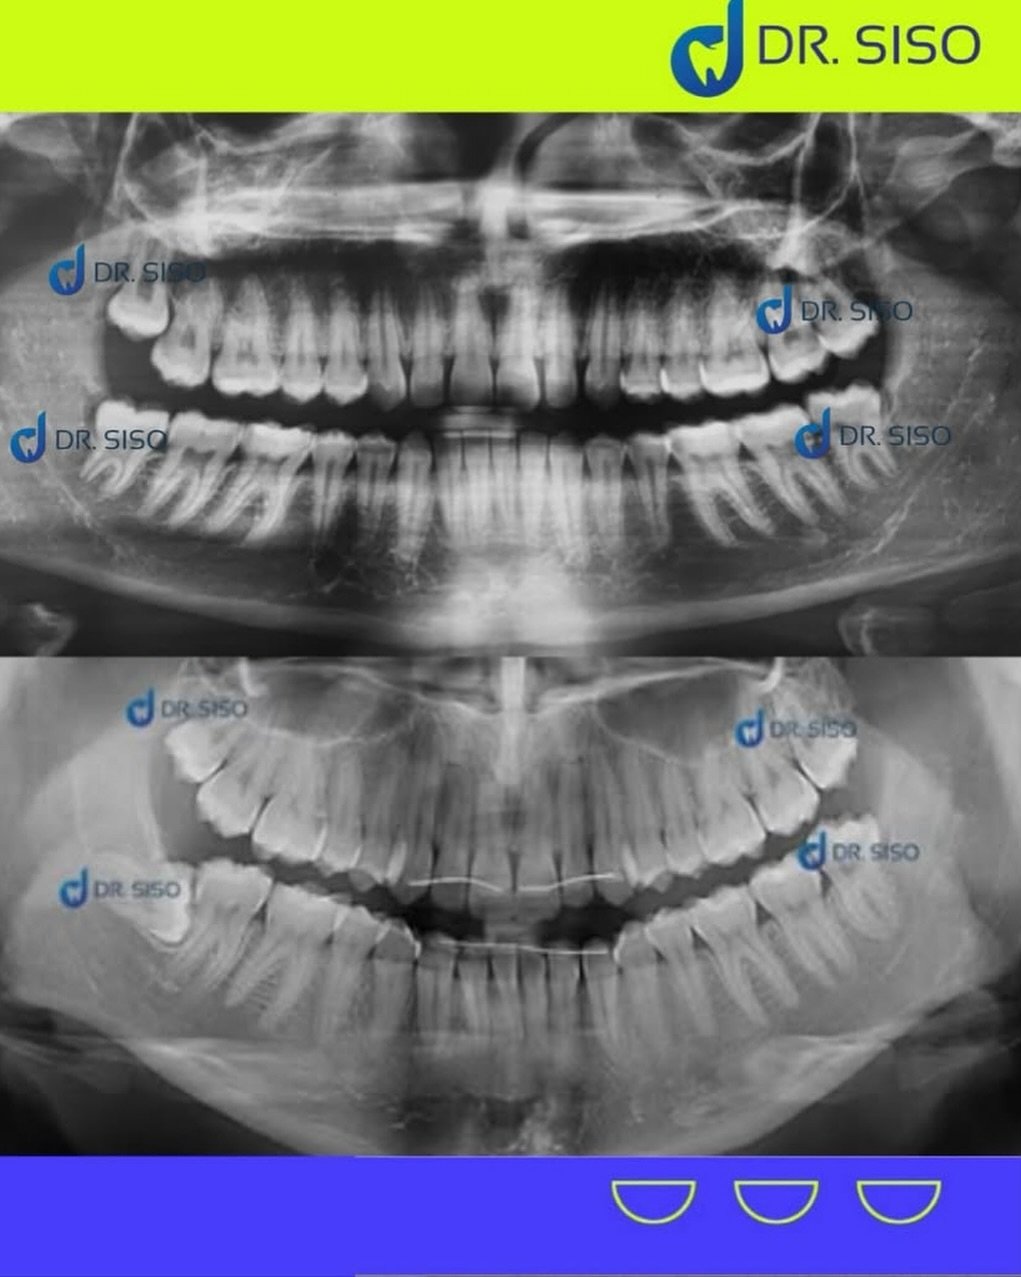

Sim, em muitos casos. Mesmo sem dor, o siso pode estar mal posicionado, pressionando outros dentes, causando reabsorção óssea ou prejudicando a mordida. A avaliação clínica e radiográfica é essencial para decidir com segurança.